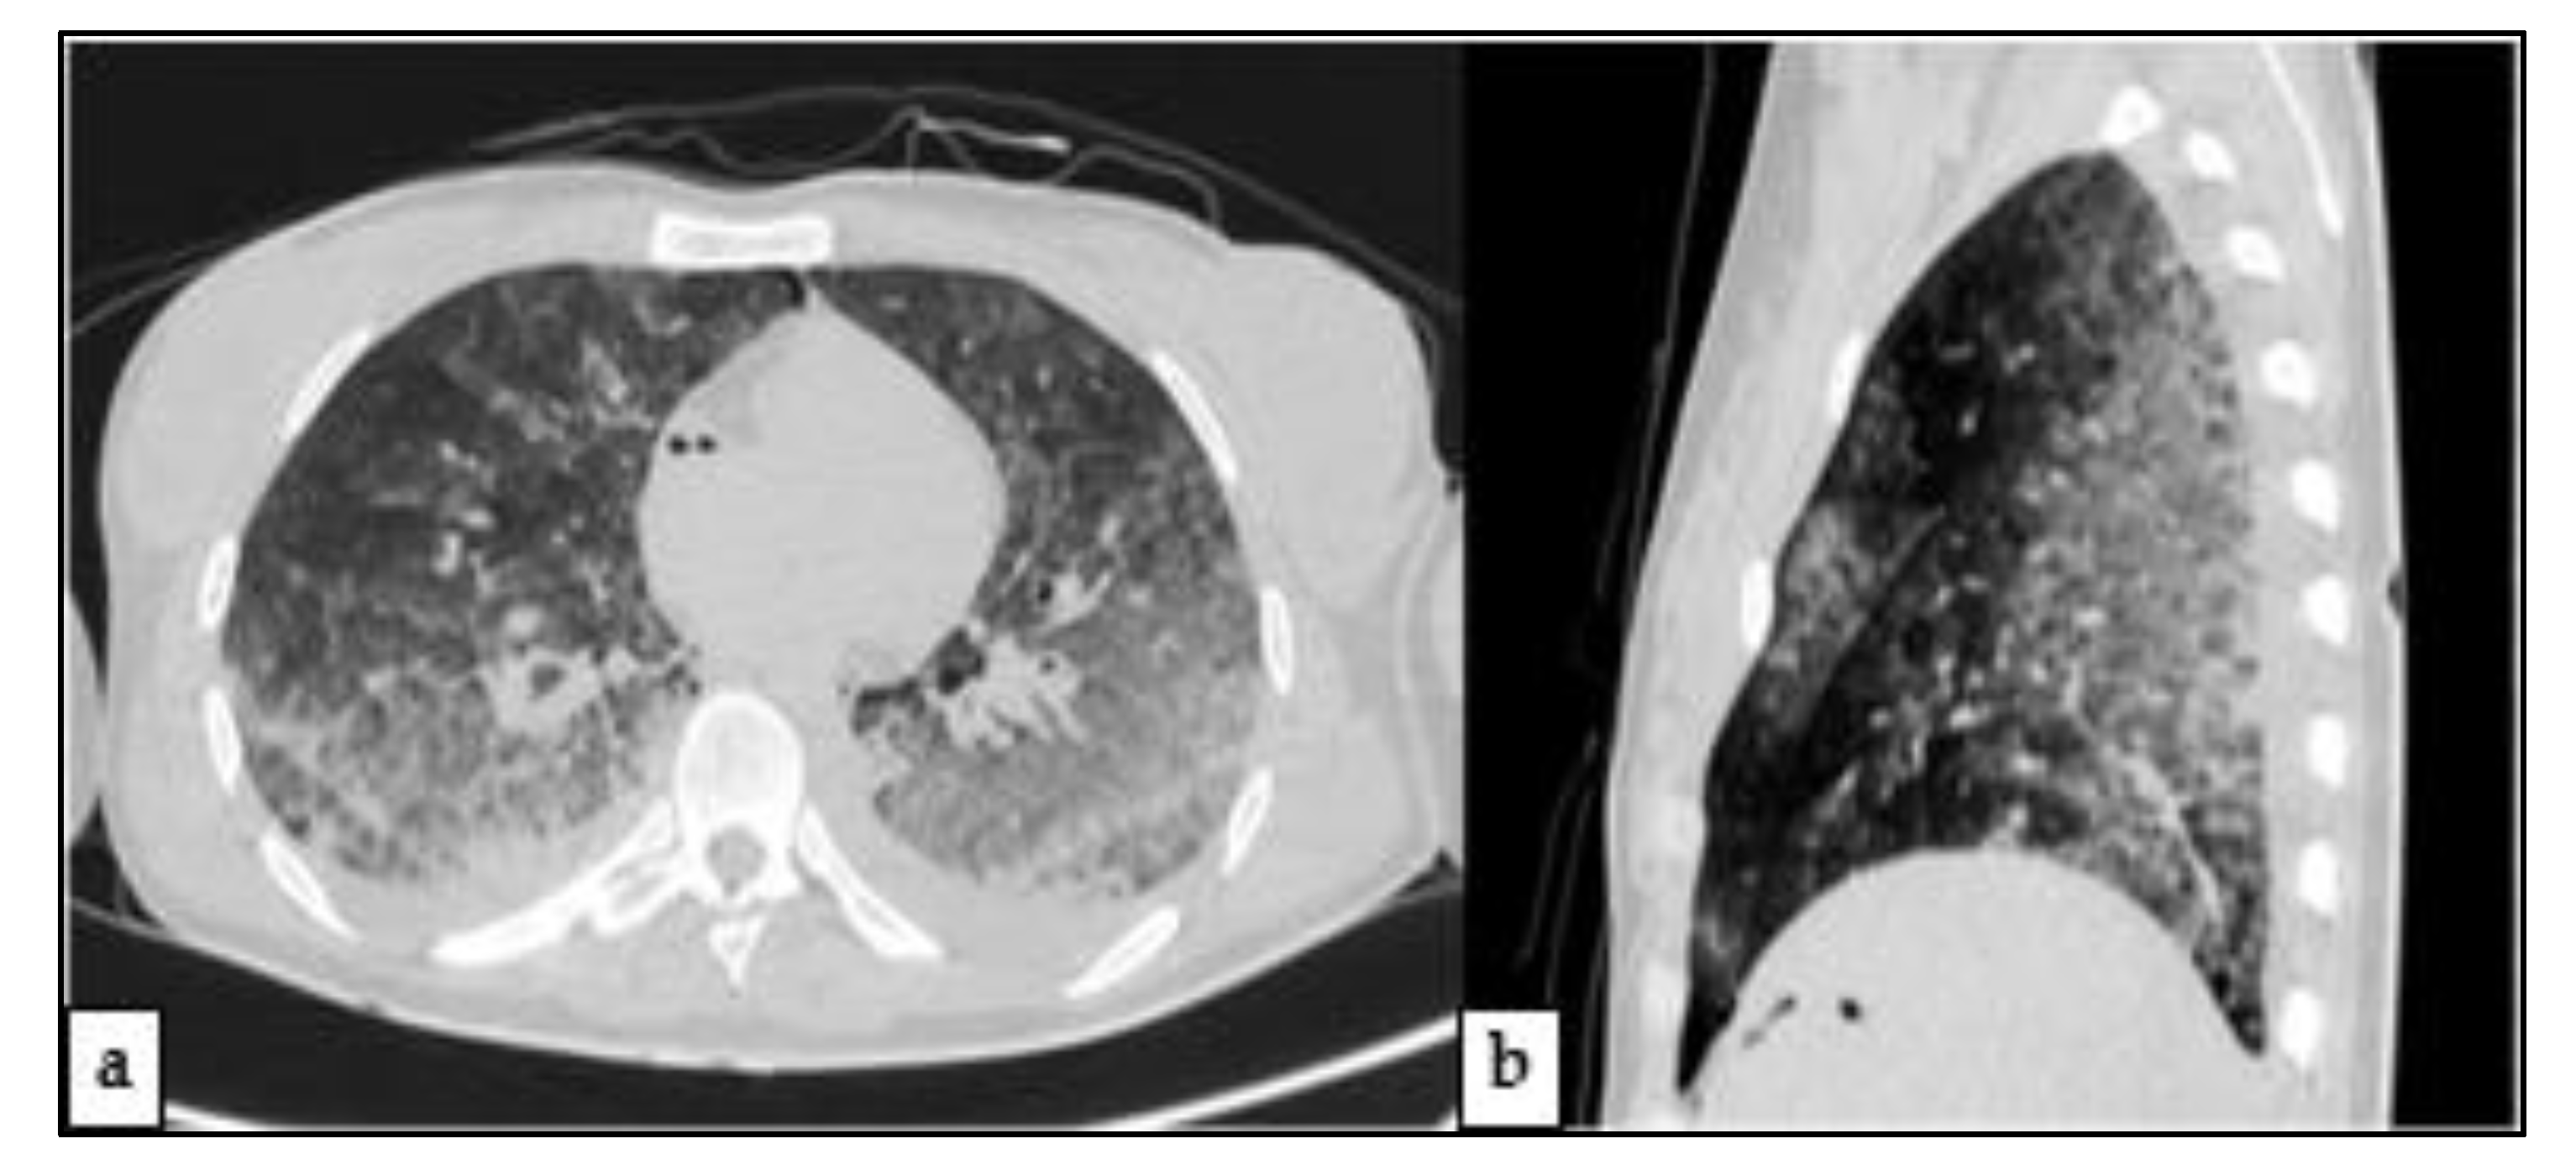

2.3. Post-Mortem Computed Tomography (PMCT)

2.4.3. Other Findings